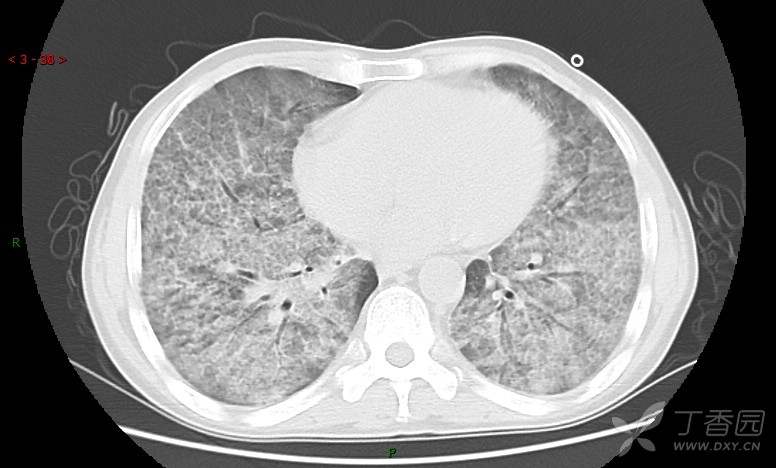

地图+铺路石征=PAP?那升高的CEA怎么说(病例3连发,附其他2例链接)

肺内弥漫性网状结节影,PET-CT却无阳性病灶,这是?(附其他2例链接)